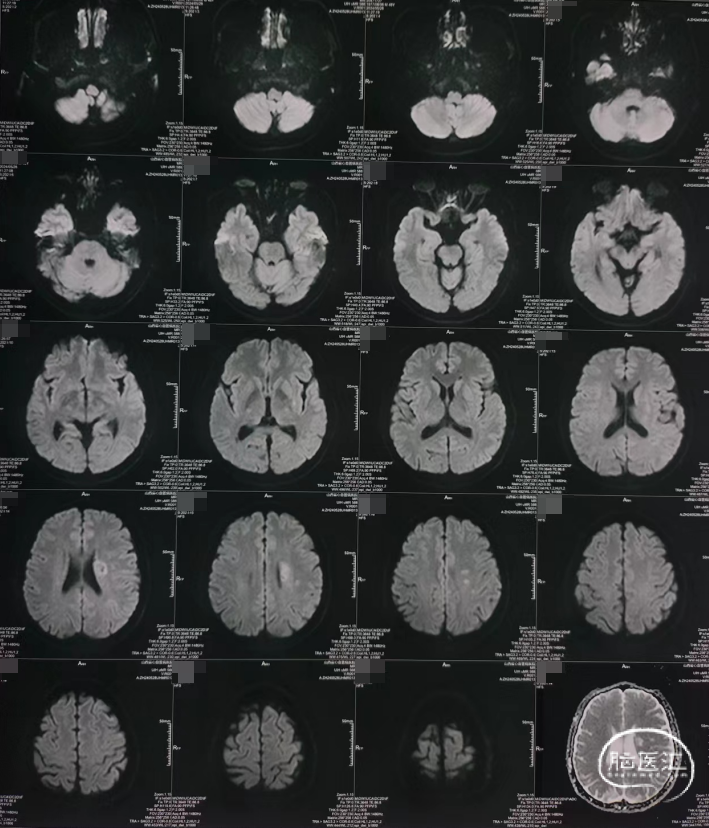

➢术前MR

核磁DWI提示:左侧侧脑室旁亚急性梗死。

核磁MRA提示:双侧大脑中动脉狭窄。